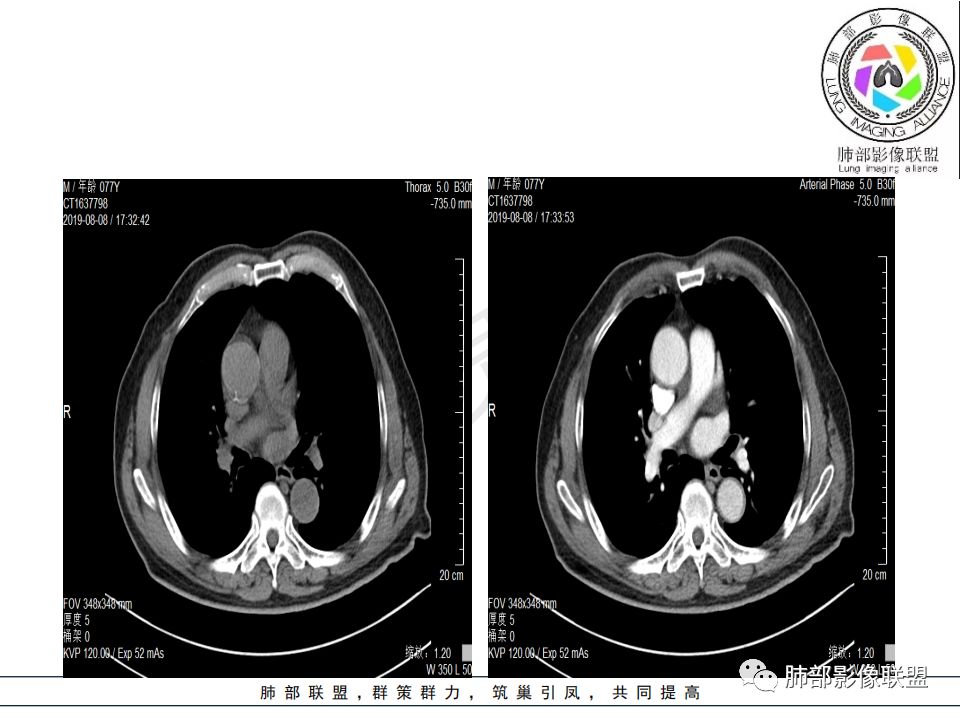

影像:影像右侧大支气管阻塞,临床没有症状或很轻微,要想到胃腺癌转移;胸壁代偿好,透亮度稍低不明显,慢性过程;34.8-52.5HU,主病灶支气管前壁另有1结节,都做成增强两期了,动脉期较平扫有强化;

晨读:患者老年男性,以咳嗽一月就诊,少量白痰,胸CT:纵隔右移,右肺体积缩小,气管下段管壁可见结节样改变,气管软骨变形,气管下段及右主支气管可见新生物向管壁浸润,并向管腔外生长,右上肺肺不张,但不张边缘可见病灶呈膨胀性生长,可见分叶,增强后强化明显。考虑:肺部恶性病变(鳞癌?)

从强化情况和冠状位看主要还是从外向内的一个肿块,有不张,但不张范围不大,近端支气管堵塞,考虑腺癌或类癌(原发或转移都可能),鉴别鳞癌。

@曹坤,河北保定清苑区人民医院ct室 肿块大,阻塞和不张范围小,强化这么大肿块没有明显坏死,鳞癌这样相对少见了

@刘鋆(福州长乐区医院)影像科 转移啊,腔外都在生长,部分通过支气管壁进入腔内

@刘鋆(福州长乐区医院)影像科 先转移生长到外面,然后进入腔内生长,也是外朝内一种,与平时那种外朝内生长逐渐侵犯近端气管没有太多区别,只不过这个是转移而已。